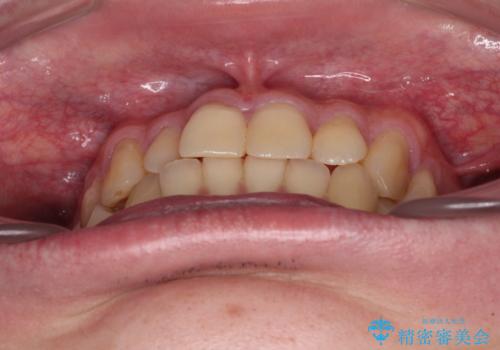

- 前歯のデコボコとクロスバイトを気にして来院された患者様です。

インビザラインでもワイヤー装置でも矯正治療は可能でしたが、煩わしい自己管理なしに短期間で治療を行いたいとのことで、目立たないワイヤー装置にて治療を行うこととしました。

- 1年1ヶ月